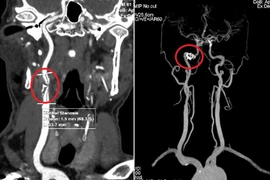

Ngoài ra, có thể áp dụng một số phương pháp khác để chẩn đoán u tuyến cận giáp như chụp cắt lớp vi tính ( CT ), chụp cộng hưởng từ ( MRI ) hoặc xạ hình tuyến cận giáp.